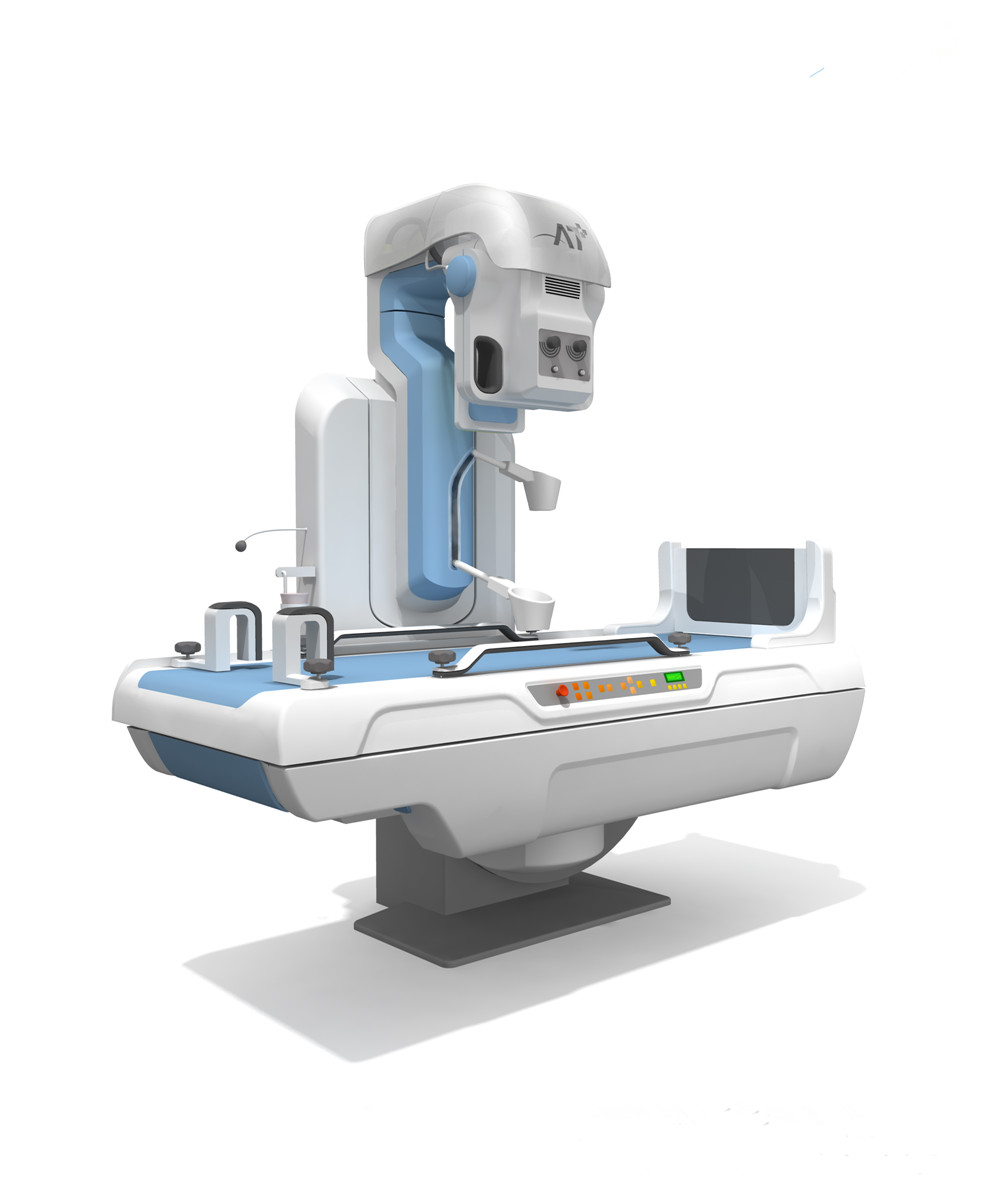

案例展示 ∥ 影像类设备 ∥ 系列放射类设备

2007年,设计团队花了近一年的时间来完成从机构到风格设计、工业设计、产品制造等全部工作。包括细节上的扶手、玻璃罩的设计,使外观更加富有设计感,但并非夸张复杂的设计风格,主要以功能为主,在满足产品功能的基础上,再进行了形式上的优化与风格的统一,我们经过与客户的紧密合作,出色地完成了客户的项目。

客户 | TCL医疗

项目 | 系列放射类设备

年份 | 2006